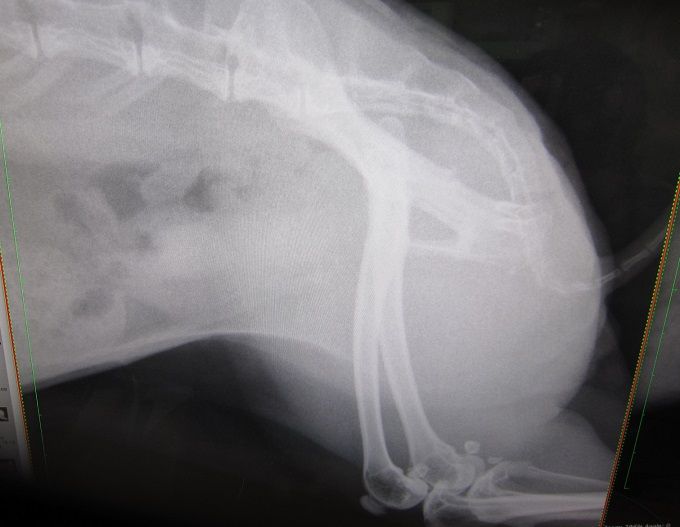

まさかあの9mmの石が出るとは…何で出たんかとかお話の前に、

まずは、石ゼロを確定させるべく早々レントゲンへ。

8.9てぇ!めちゃデカなってるし!

すんごい早くない?あまりにデカなるの早すぎひん

向かって左が今回、右がこないだ。

光の加減で膀胱全体が白っぽく見えますが石はありませんっ

石はありませんっ